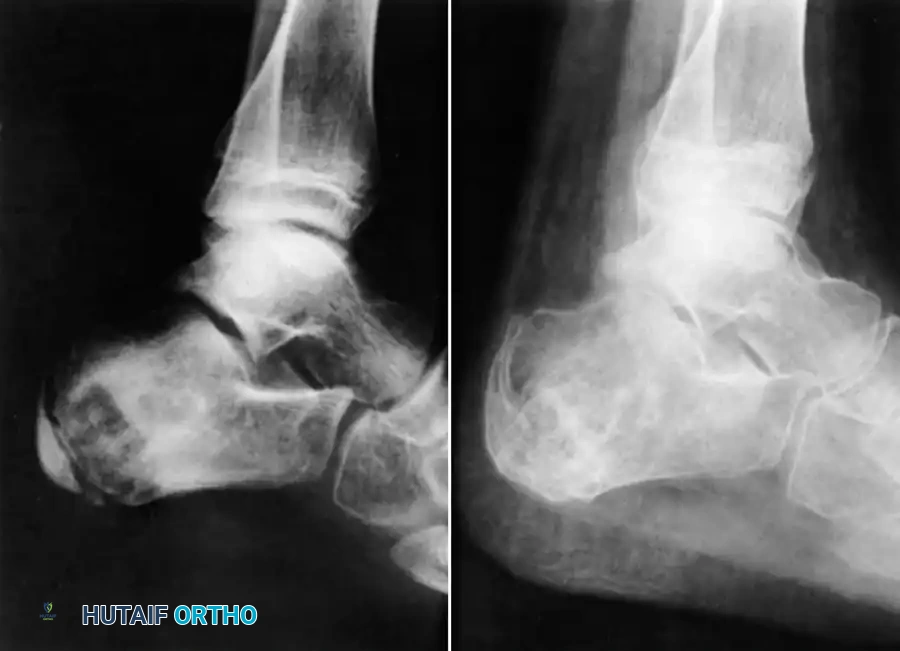

The Foot and Ankle

Tuberculosis of the foot and ankle often presents with midfoot swelling, sinus tract formation, and severe pain upon weight-bearing. The calcaneus and talus are frequently involved, presenting with cystic, lytic lesions that can compromise the structural integrity of the hindfoot.

Advanced imaging, as seen above, often reveals extensive midfoot destruction and soft-tissue abscess formation. Surgical management in the early stages involves aggressive tenosynovectomy and curettage of lytic lesions. Bone grafting may be required to fill cavitary defects in the calcaneus.

In advanced cases with articular collapse, arthrodesis is the treatment of choice. For midfoot and hindfoot involvement, a triple arthrodesis or tailored midfoot fusion is performed to restore a plantigrade, stable foot.